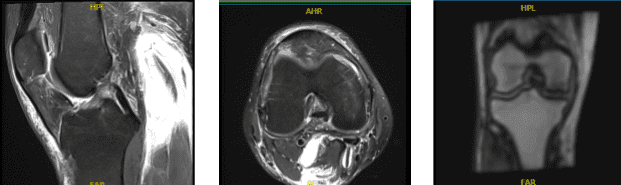

MRI Right Knee Non-contrast

Examination of the menisci reveals a tear of the posterior horn of the medial meniscus with abnormal signal within the posterior horn which contacts the inferior articular surface. No tears are seen within the lateral meniscus. The anterior and posterior cruciate and medial and lateral collateral ligaments appear intact.

The patellar and quadriceps tendons appear intact. There is a small joint effusion. The distal femur, proximal tibia and fibula, and patella appear intact without evidence of any fractures, contusions, or bony lesions. The popliteal fossa is clear. There is prepatellar and pretibial soft tissue edema.